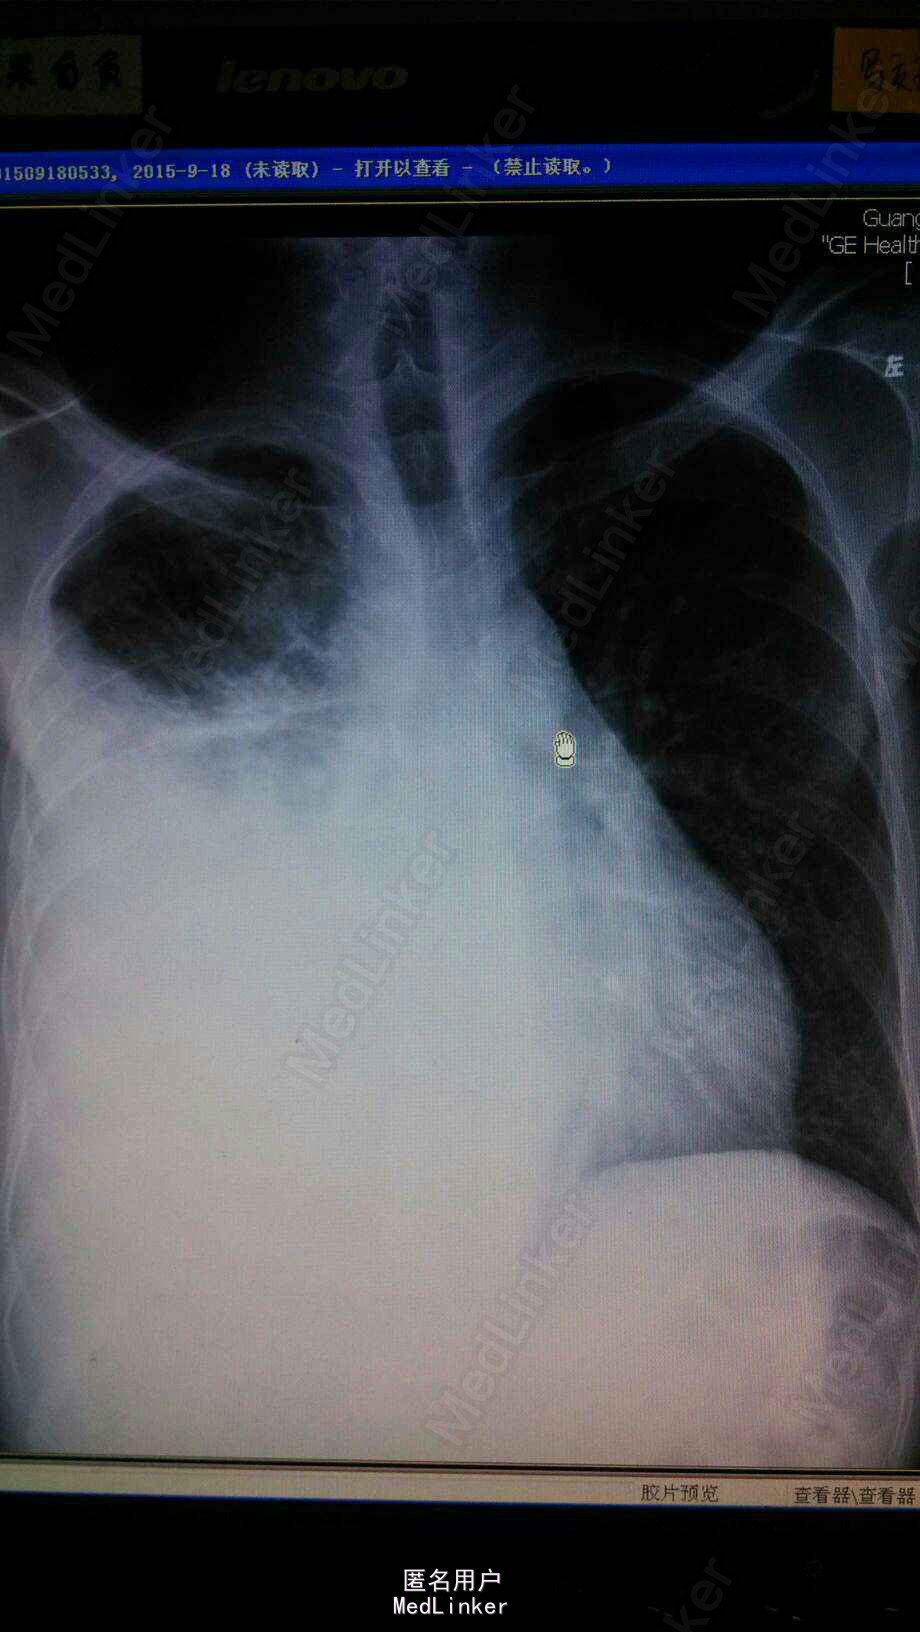

查体右下肺呼吸音减弱,无干湿罗音。心音正常。胸片示右胸膜增厚,少量积液。行胸膜活检示胸膜恶性间皮瘤。

患者治疗6周期后,因经济原因停止化疗。今年复查胸片示右肺大量实变,b超证实非胸水。考虑为肿瘤进展。胸膜间皮瘤往往以胸水为首发,易误诊漏诊,对反复胸水治疗效果欠佳者,应尽早应胸膜活检。胸膜间皮瘤最佳治疗方案是力比泰。